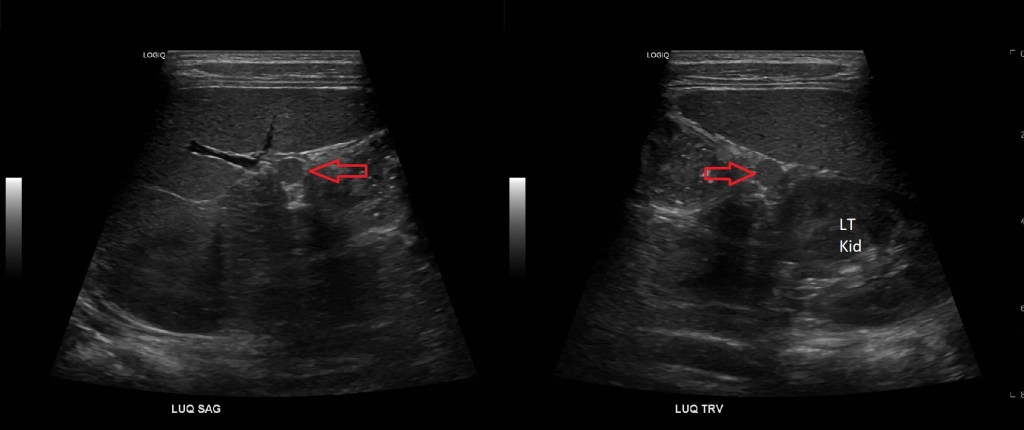

An accessory spleen is normal splenic tissue separate from the main mass of the spleen. Accessory spleens vary in size from a few millimeters to several centimeters, they occur most frequently near or at the splenic hilum. They are also quite common found in up to 16% of CTs of the abdomen and up to 30% of autopsies [1]. For the uninitiated the splenule may be mistaken for a tumorso it is important that the sonographer is aware of this variant. Splenunculi also occur post splenectomy, and may enlarge, although they usually retain a spherical shape. [2]

The most common location to find a splenule is by the splenic hilum however they have been documented in other parts of the body as close as the stomach and pancreas and as far as the scrotum. [3,4]